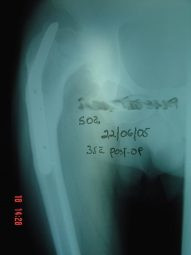

Prótesis Total de Cadera

Envíado por Dr. Ricardo Antonio Gómez G.